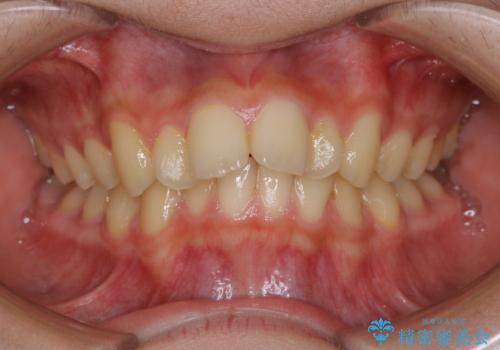

- 患者様、出っ歯のお悩みで来院されました。

骨格の分析を行ったところ上顎も出てはいるのですが、下顎が引っ込んでいる状態であるということがわかりました。

よって上顎の歯を抜いて治療をするのではなく、カリエールという器具を使用して下顎を前に引っ張り出しながら上顎を引っ込めるという治療を行うことにしました。